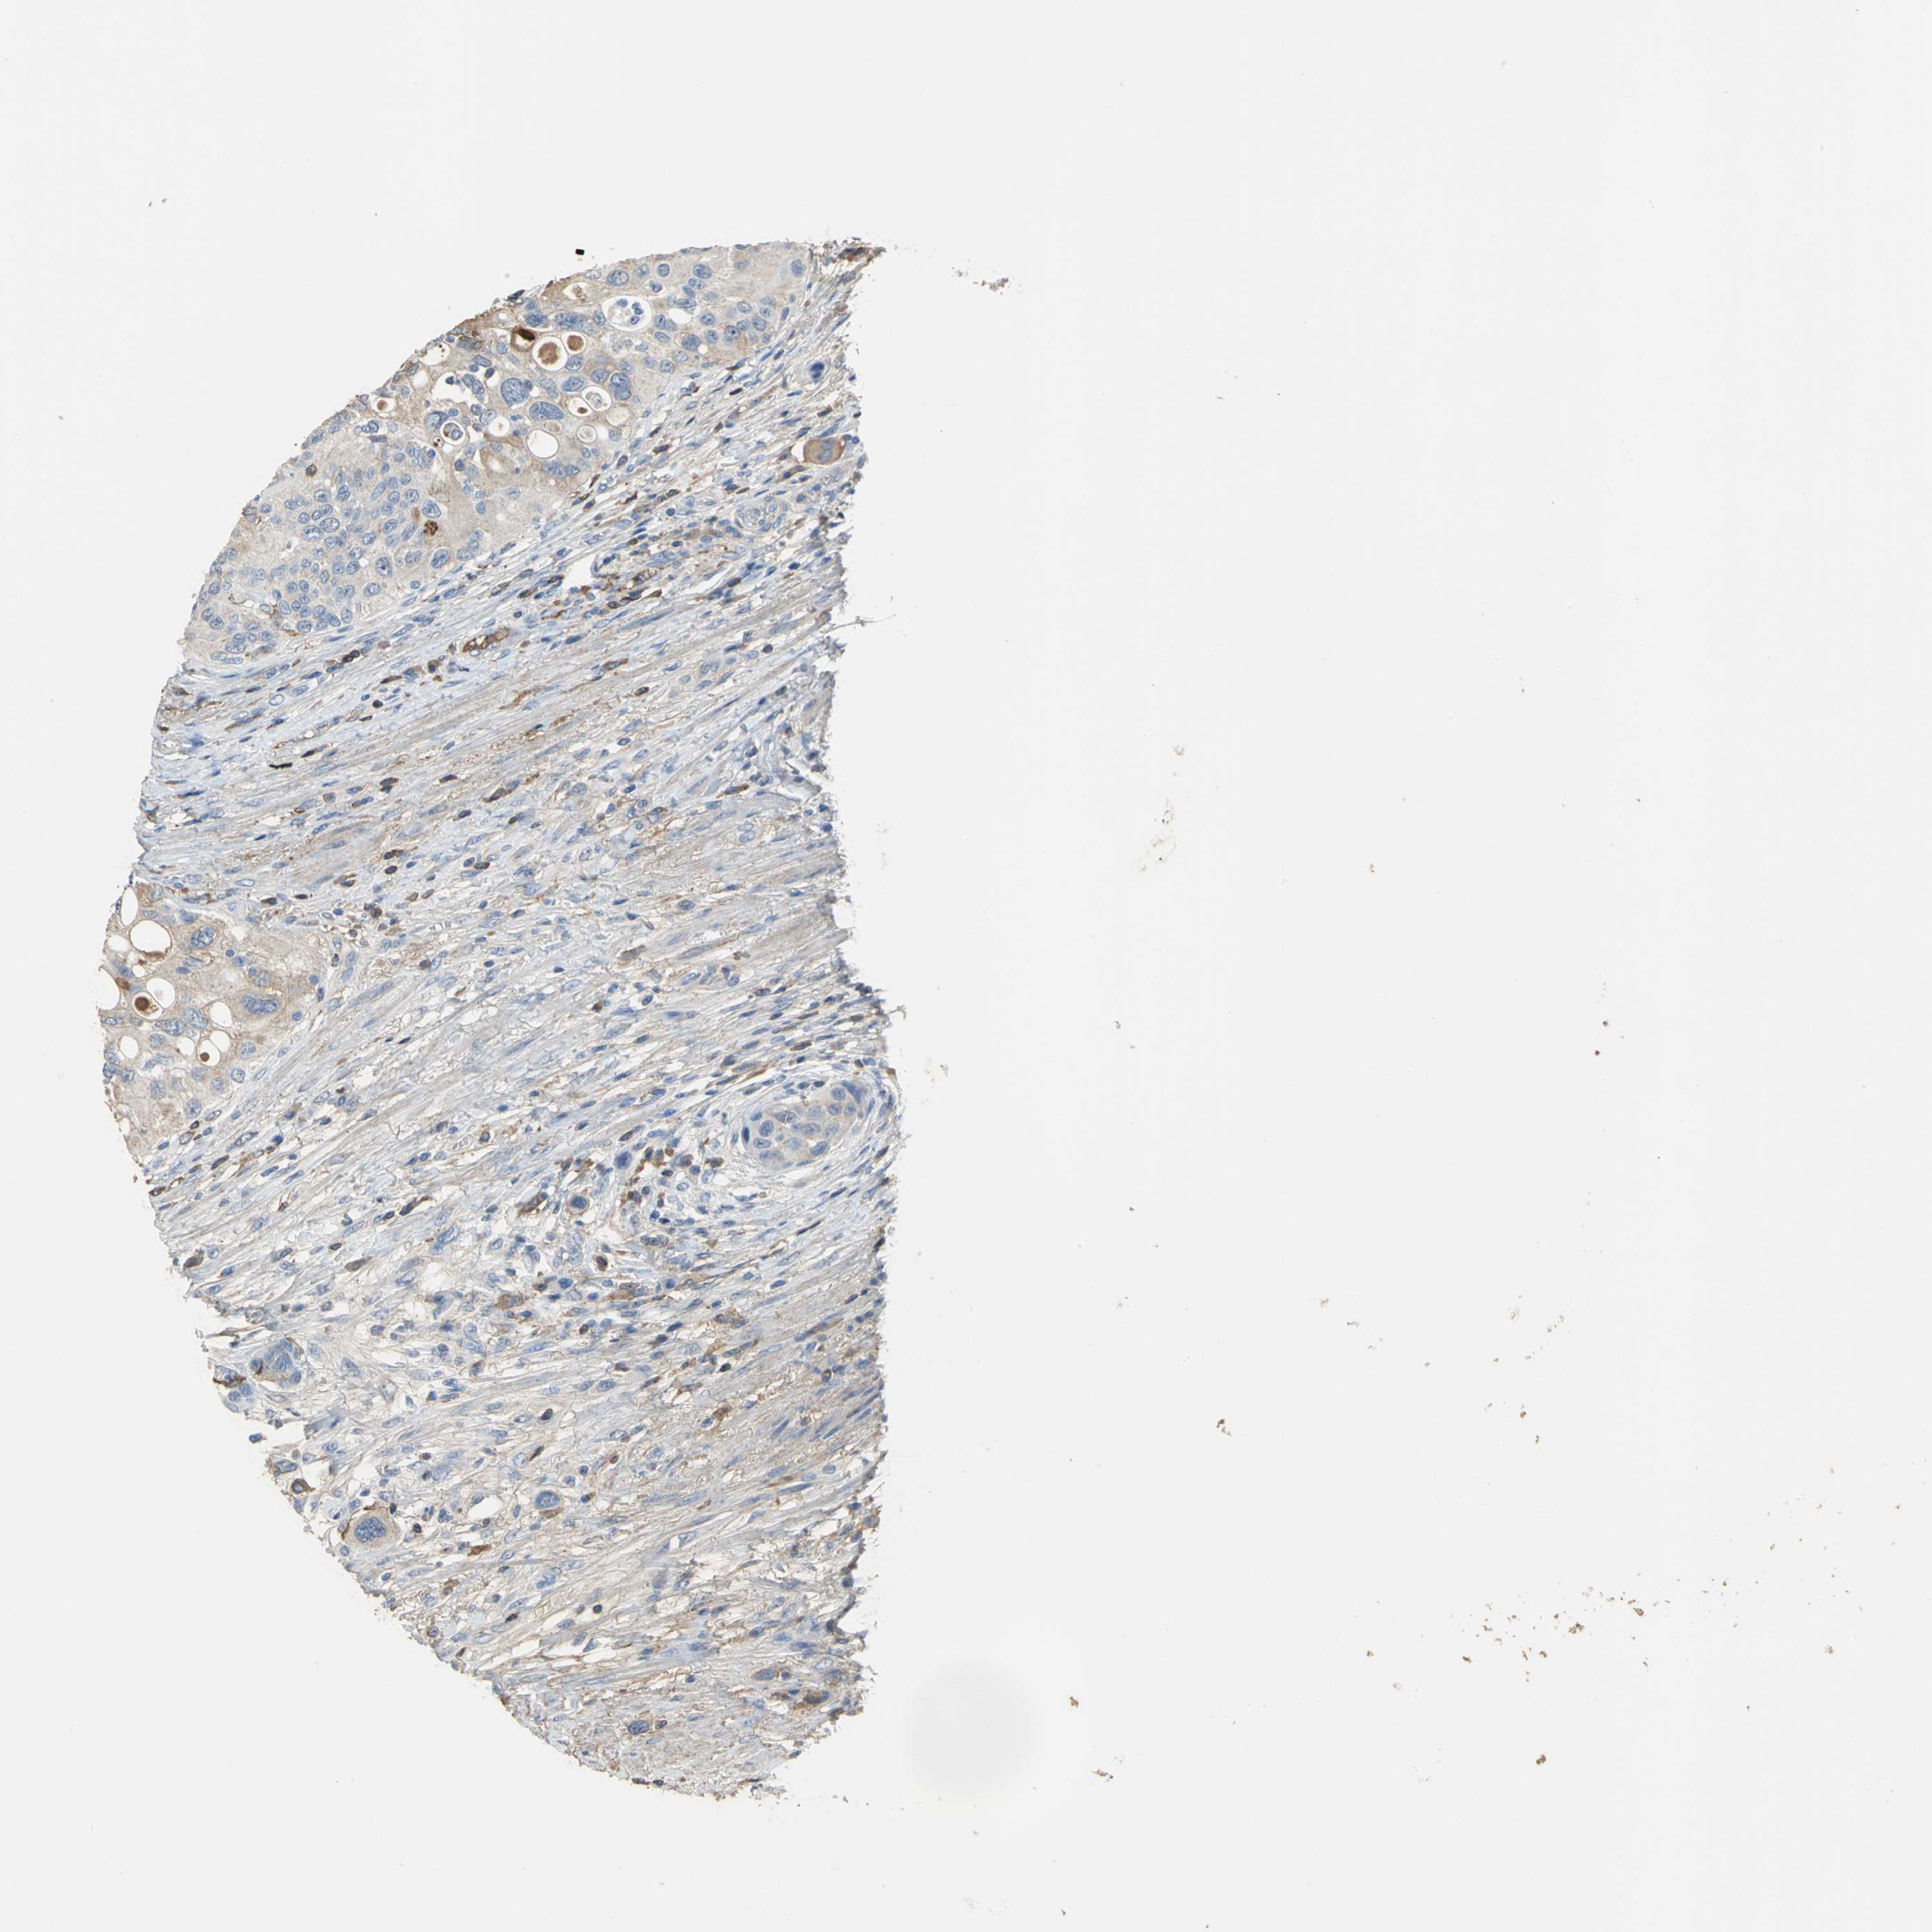

UROTHELIAL CANCER - Protein expressioni

A mouse-over function shows sample information and annotation data. Click on an image to view it in a full screen mode. Samples can be filtered based on level of antibody staining by selecting one or several of the following categories: high, medium, low and not detected. The assay and annotation is described here.

Note that samples used for immunohistochemistry by the Human Protein Atlas do not correspond to samples in the TCGA dataset.

Antibody stainingi

Antibody staining in the annotated cell types in the current human tissue is reported as not detected, low, medium, or high, based on conventional immunohistochemistry profiling in selected tissues. This score is based on the combination of the staining intensity and fraction of stained cells.

Each image is clickable and will lead to virtual microscopy that enables deeper exploration of all samples and also displays staining intensity scores, fraction scores and subcellular localization as well as patient and tissue information for each sample.

Antibody HPA005495

Antibody HPA064686

Staining

High

Medium

Low

Not detected

Intensity

Strong

Moderate

Weak

Negative

Quantity

>75%

75%-25%

<25%

None

Location

Nuclear

Cytoplasmic/membranous

Cytoplasmic/membranous,nuclear

Urothelial carcinoma, High grade

Urothelial carcinoma, Low grade

Urothelial carcinoma, NOS